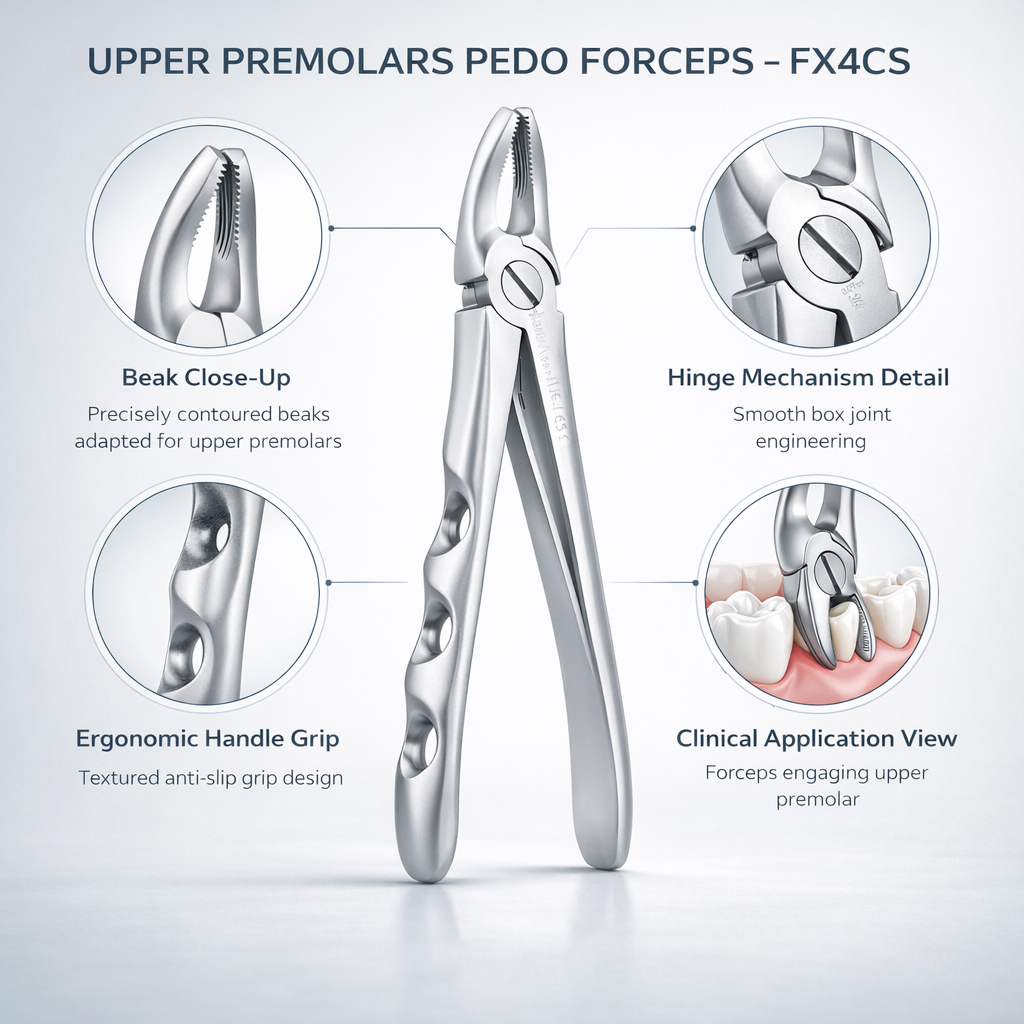

Pedo Extraction Forceps: These specialized forceps are designed to extract deciduous (baby) teeth gently. They have smaller, anatomically adapted beaks that fit comfortably around the smaller roots of baby teeth, reducing the risk of trauma during extraction. The handles are designed for easy grip and better control, ensuring a safe and efficient extraction process.

Pedo American Forceps: These forceps are designed to grip and extract deciduous teeth that are mobile or need removal. They have unique beak designs that cater to the varying shapes and sizes of baby teeth, providing a secure hold for extraction while minimizing any discomfort for the child.